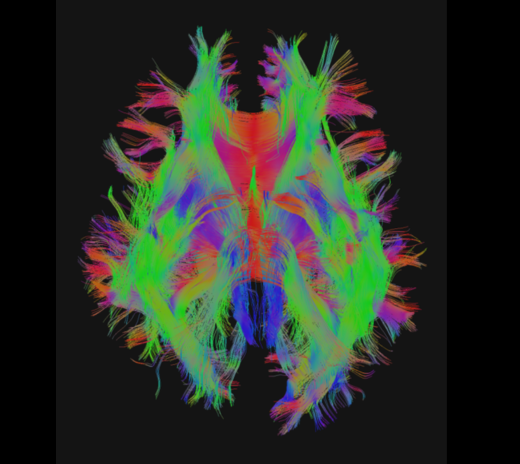

磁力共振扫描影像(脑部扩散张量造影)